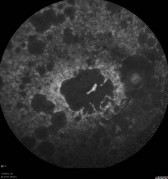

The subretinal microchip implantation involves placing a 1500-electrode microchip just below the retina, specifically in the macular region. Results of Retina Implant's first human clinical trial were published in the prestigious peer-reviewed journal Proceedings of the Royal Society B and showed placement of the implant below the retina, in the macular region, provided optimum visual results allowing patients to recognize foreign objects and to read letters to form words.

Post-implantation, the microchip is turned on - this is when the evaluation of sight restoration begins. As patients must develop new internal processes for interpreting the images they see, it typically takes several weeks to fully realise their new sight capabilities.